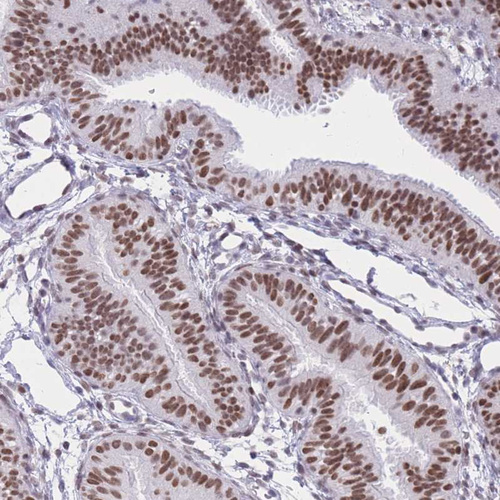

Immunohistochemical staining of human tonsil shows strong nuclear positivity in non-germinal center cells and germinal center cells.